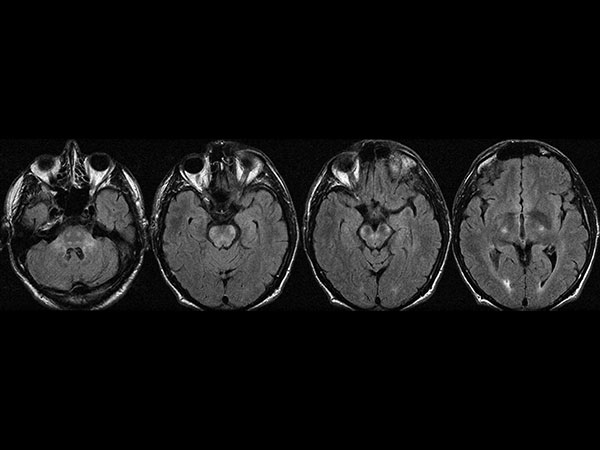

இந்த நோயால் பாதிக்கப்பட்ட மக்களின் 40% மக்கள் நரம்பு சம்பந்தமான பிரச்சினைகள், கண்களில் பாதிப்பு மற்றும் முக தசைகளில் பிரச்சினைகள், டிமென்ஷியா, வலிப்பு, நினைவாற்றல் இழப்பு, பலவீனம் மற்றும் தலைவலி போன்ற ஏகப்பட்ட பிரச்சினைகள் ஏற்படும். இந்த தீவிரமான நோயின் அறிகுறிகள், சிகிச்சைகள் பற்றி இங்கே காணலாம்.

நரம்பு மண்டலத்தில் ஏற்படும் அறிகுறிகள்

இன்ஸோமினியா

டிமென்ஷியா

முகத்தில் உணர்வின்மை

கண்களில் பிரச்சினை

காது கேட்காமல் போகுதல்

நினைவாற்றல் இழப்பு

அசைய முடியாமல் போதல்.

நோயாளிகளுக்கு ஆன்டிபாயாடிக் மருந்துகள் கொடுத்து தொற்றை சரி செய்கின்றனர். சில சமயங்களில் 1 அல்லது 2 வருடங்கள் வரை கூட சிகச்சை அளிக்கப்படுகிறது. மூளை மற்றும் நரம்பு மண்டலம் பாதிக்கப்படாமல் இருந்தால் ஆன்டி பயாடிக் மருந்துகளைக் கொண்டே சரி செய்து விடலாம்.

ஆன்டி பயாடிக் மருந்துகள் மூலம் உடலில் உள்ள பாக்டீரியாக்களை அளிப்பதோடு, மூளை மற்றும் நரம்பு மண்டலத்திலும் பாக்டீரியாக்கள் நுழைந்து இருந்தால் அதற்கும் சிகிச்சை அளிக்க வேண்டியது அவசியம்.